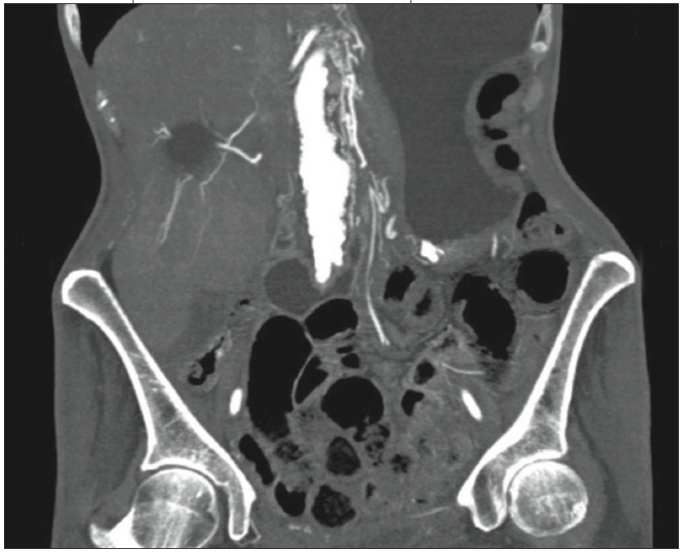

Figure 1 – This CT scan demonstrates two of the findings of mesenteric isch- emia: intramural air (pneumatosis intestinalis) and thrombus in the superior mesenteric artery.

CT findings are often normal or nonspecific. However, CT can help evaluate other causes of abdominal pain. Specific findings include pneumatosis intestinalis, portal venous gas, abnormal bowel enhancement, and mesenteric vessel occlusion (Figure 1). The most common finding is bowel wall thickening or edema. The sensitivity is between 64% and 87% for identifying mesenteric ischemia on CT.10